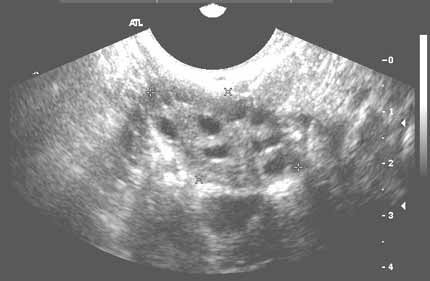

Right ovary - transvaginal showing follicular cysts

Note: Images are shown for illustrative purposes. Do not attempt to draw conclusions or make diagnoses by comparing these images to other medical images, particularly your own. Only qualified physicians should interpret images; the radiologist is the physician expert trained in medical imaging.